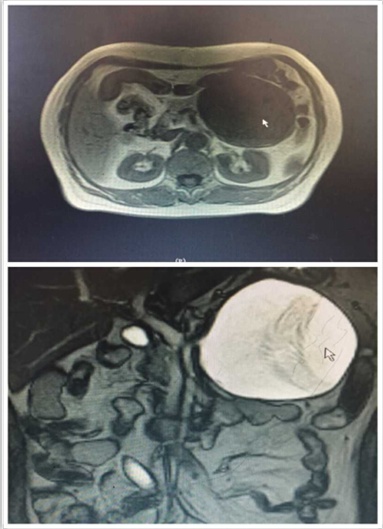

近日,我院肝膽外科入住一位65歲老年女性患者。該患者是一位退休工人,平日生活樸素,一年前自覺有上腹部隱痛不適,每次腹痛發(fā)作便自行于藥店買藥“治療”??墒墙螘r間,該患者感覺腹痛進行性加重,腹部出現(xiàn)隆起,進食少量食物便會出現(xiàn)腹脹、惡心、嘔吐不適,遂來我院就診。門診行腹部CT檢查發(fā)現(xiàn)胰腺巨大占位性病變(圖1),此時患者才恍然大悟,立即入住肝膽外科進行治療。

圖1